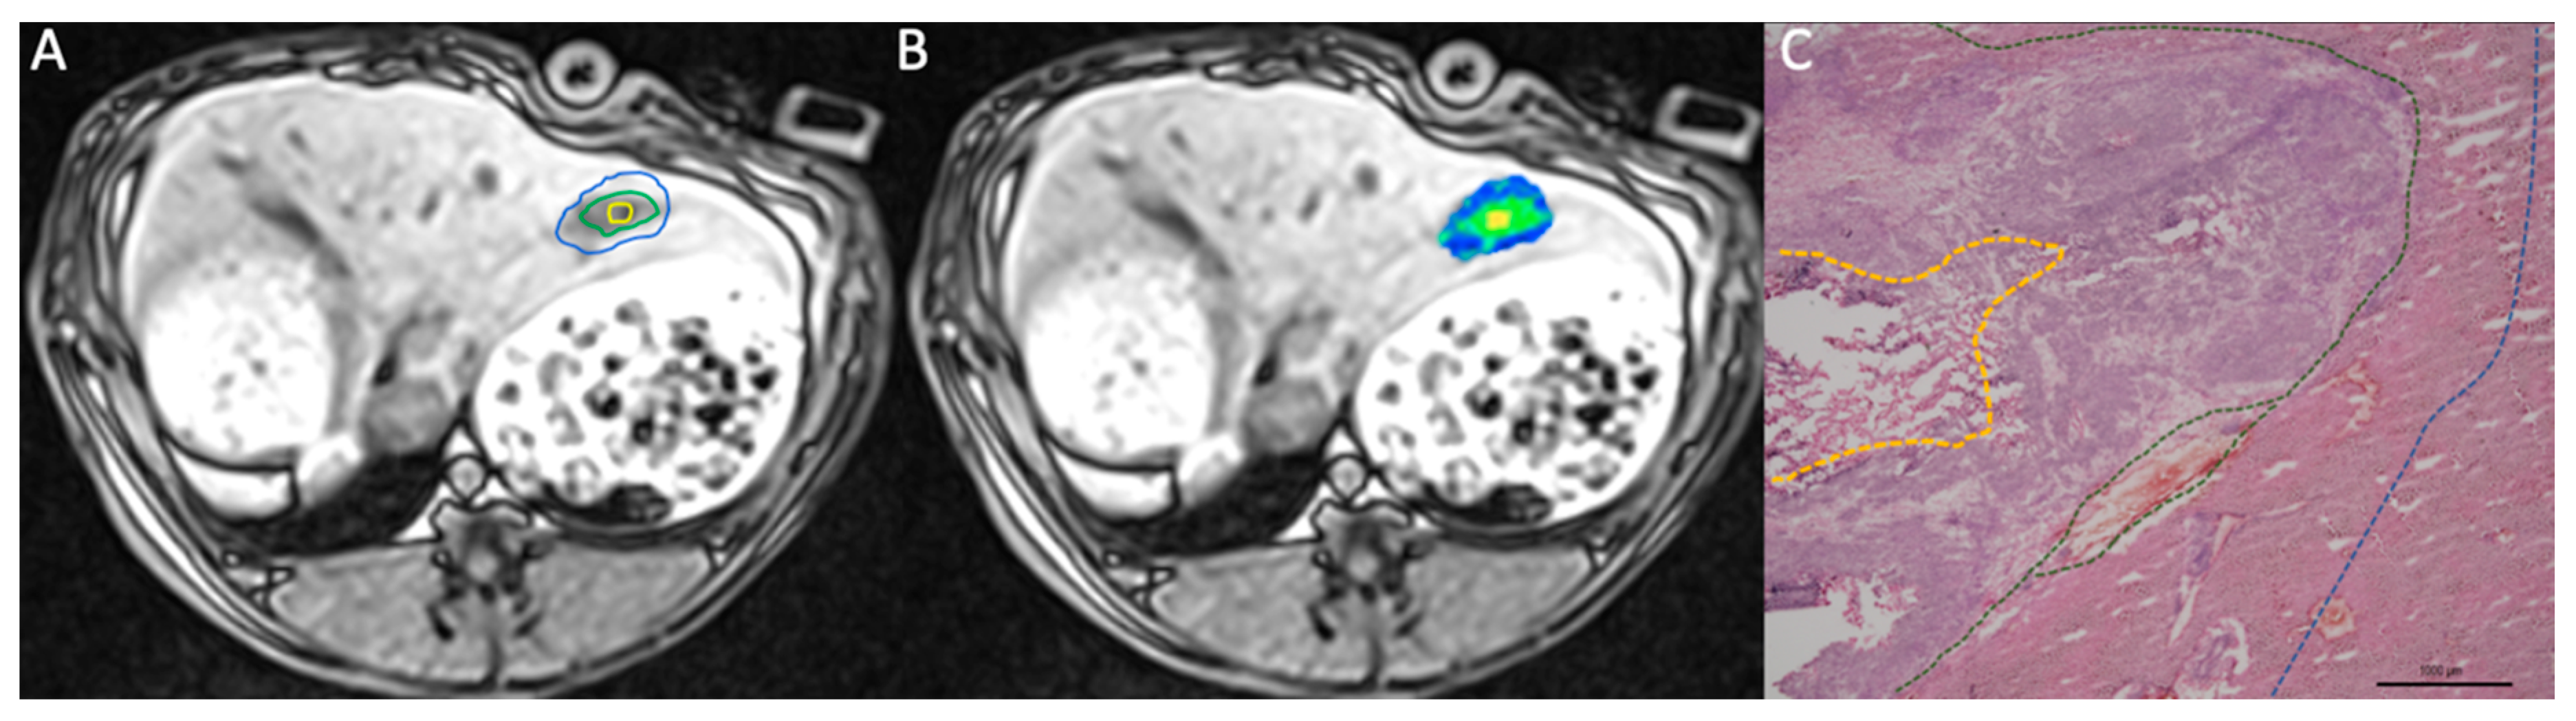

3.1. Native T1 Mapping

3.2. Histopathological Analysis